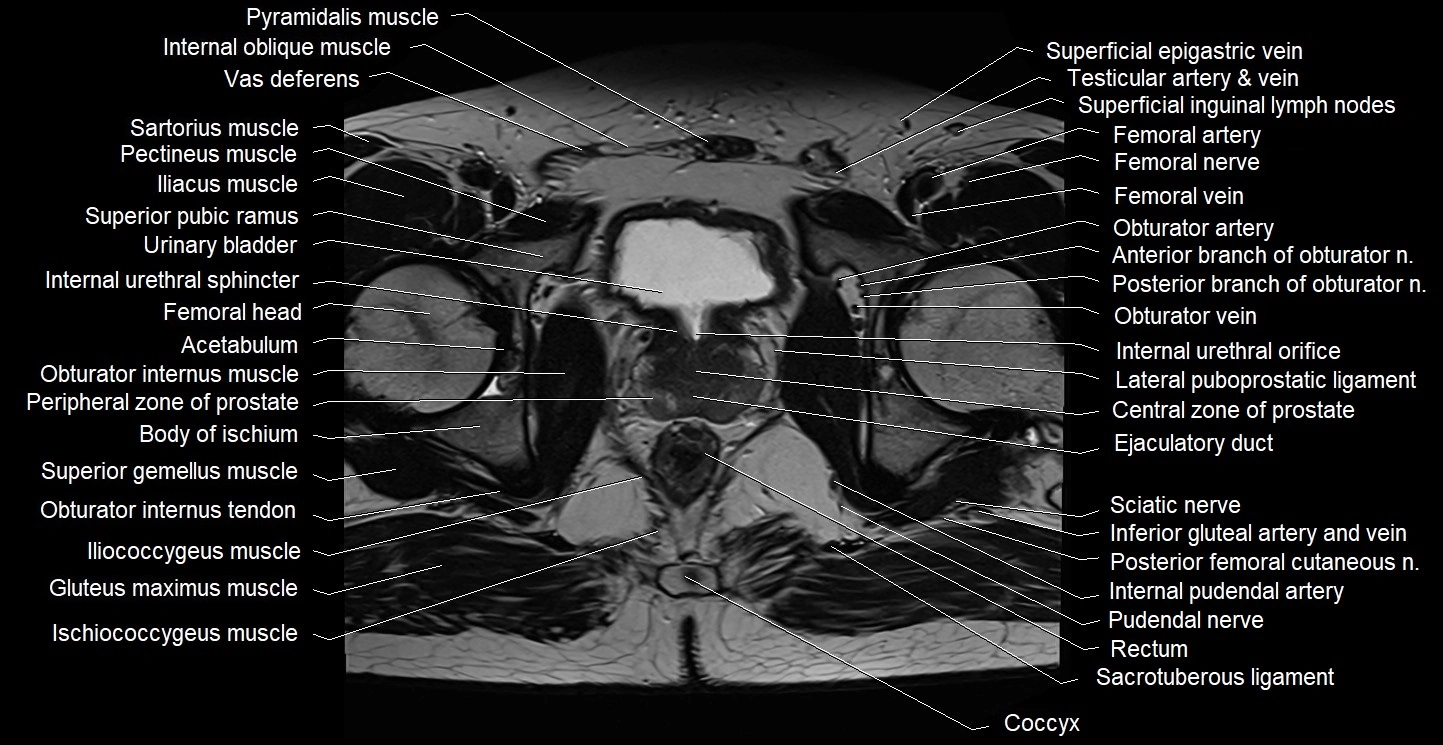

- Acetabulum

- Body of ischium

- Central zone of prostate

- Co (Coccyx)

- Coccyx

- Ejaculatory duct

- Gluteus maximus muscle

- Gluteus medius muscle

- Gluteus minimus muscle

- Iliococcygeus muscle

- Inferior gemellus muscle

- Internal pudendal artery

- Internal pudendal vein

- Internal urethral sphincter (male)

- Ischiococcygeus muscle

- Levator ani muscle

- Mesorectum

- Obturator internus muscle

- Obturator internus tendon

- Obturator nerve

- Obturator vein

- Pectineus muscle

- Peripheral zone of prostate

- Piriformis muscle

- Posterior femoral cutaneous nerve

- Pudendal nerve

- Rectum

- Sacral plexus

- Sacrotuberous ligament

- Sciatic nerve

- Superficial inguinal lymph nodes

- Superior gemellus muscle